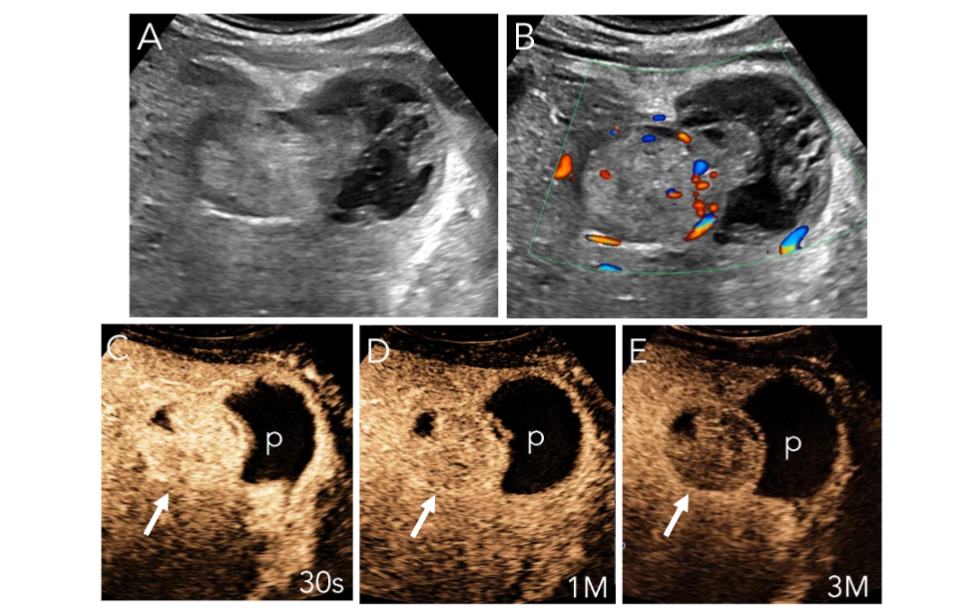

40-year-old male with HBV and abdominal pain.

A) Greyscale US shows large solid mass with hypoechoic, exophytic extension, suggesting fluid.

B) Color doppler imaging shows some blood flow peripherally within the mass.

C) CEUS at 30s shows APHE within the mass (arrow) and a large avascular pocket (p).

D) There is sustained enhancement of the mass at 1M (arrow).

E) At 3 minutes there is weak late washout of the mass.

CEUS enhancement pattern suggests HCC, with spontaneous rupture and hematoma. This was a confirmed ruptured HCC on pathology.

Figure 7: Ruptured HCC